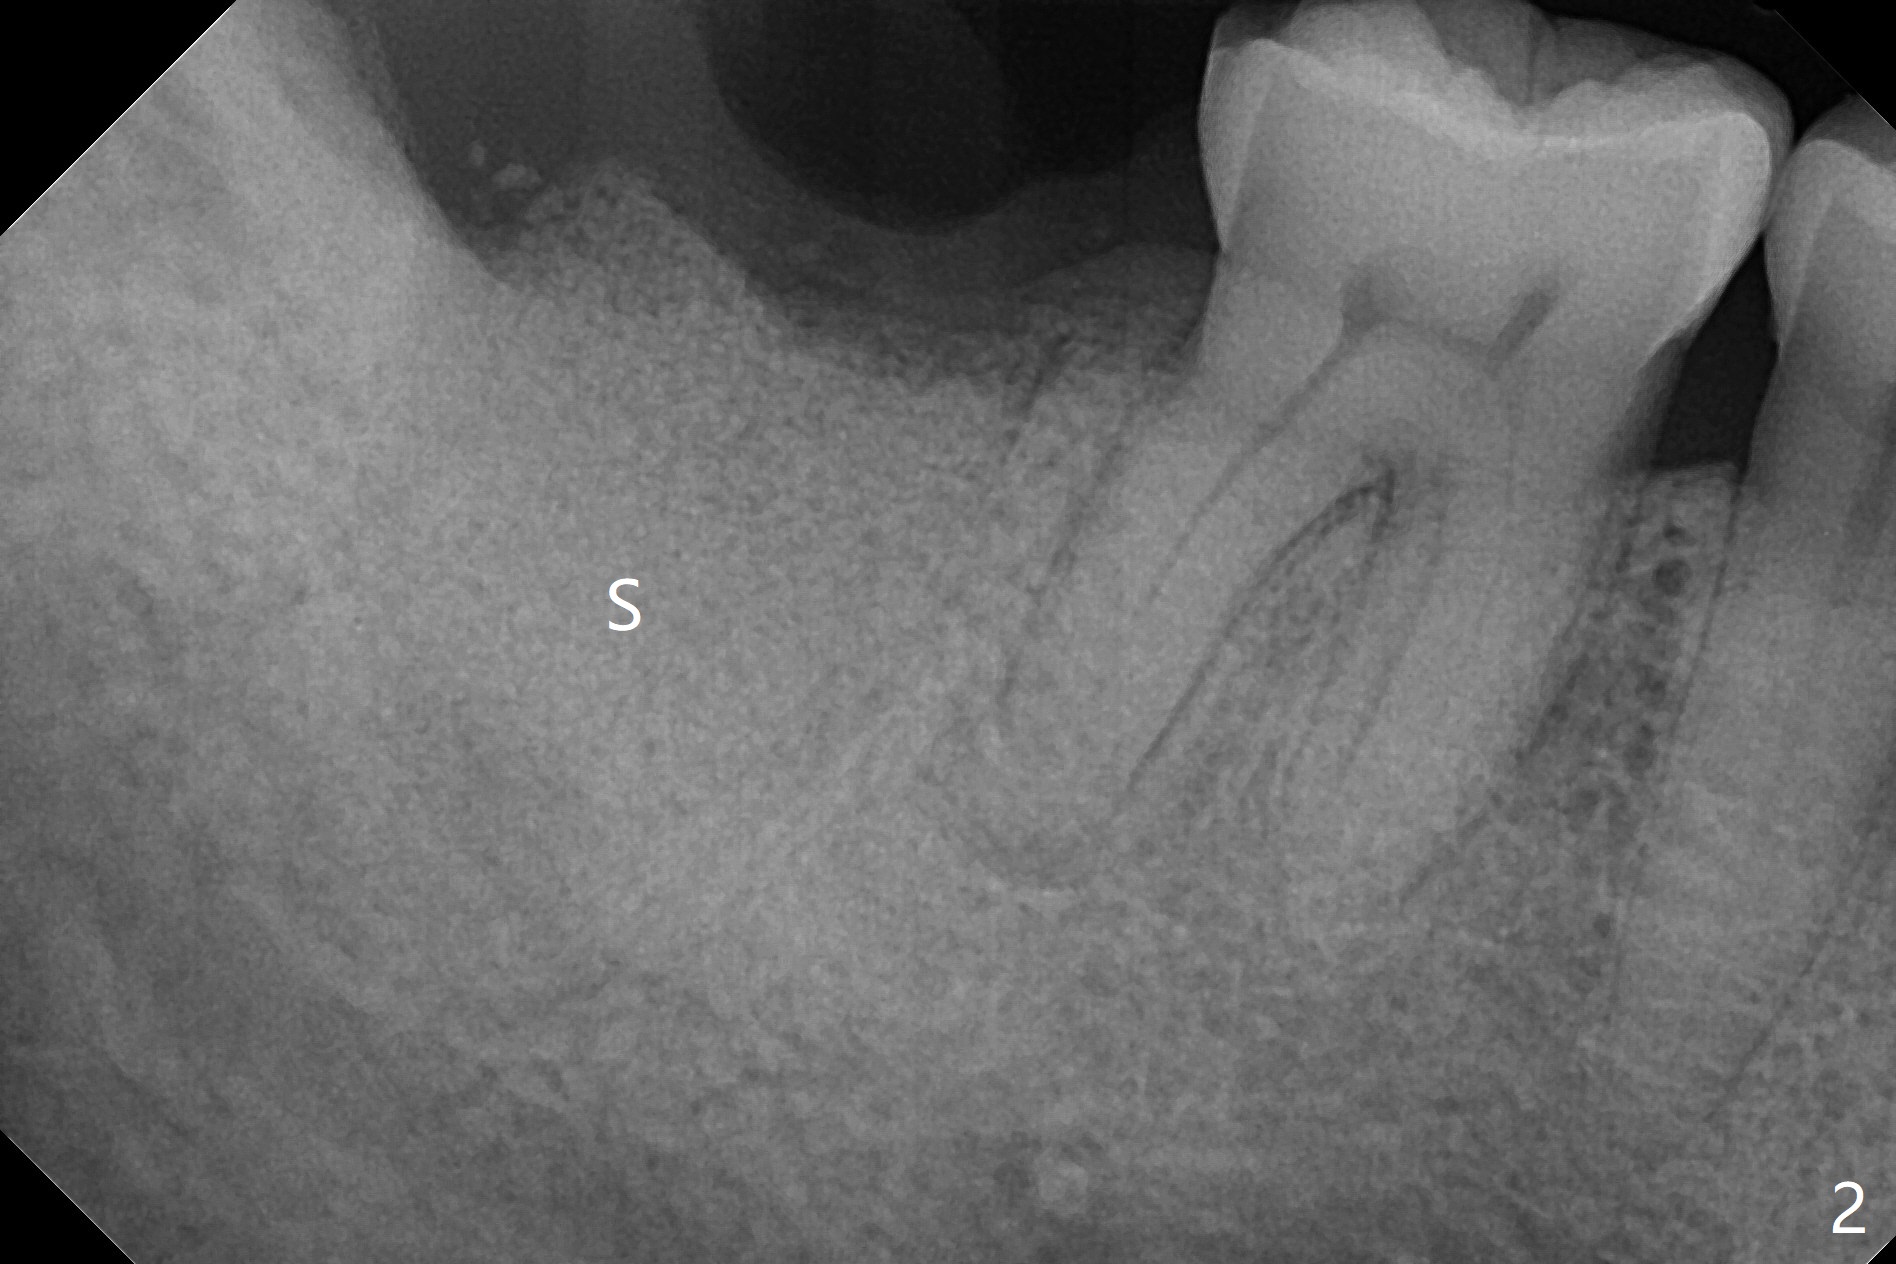

今天特别忙,第一位病人深洗后需要拔除智齿,事先准备使用胶原塞,但是术后发现缺损太大,需要植骨,匆忙使用GEM21S与细颗粒骨粉调袢,需要用大号输送器送到口内,骨粉容易散开,不便利。几个小时后,63岁女急诊要求拔除右下第二磨牙(图一),开始我们准备也使用GEM21S,但是没有大号输送器,改为抽血,制备粘性骨粉,很方便用镊子将骨块输送到牙槽窝(图二:G),上面覆盖PRF膜和不可吸收膜,PTFE缝线,由于缝合比较密,不需要牙周敷料。